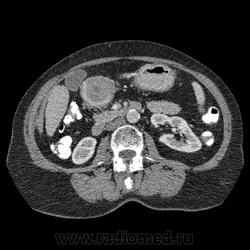

Впечатление, что дуля эта вне головки п.ж., интрамурально в луковице, что ли... тогда возможно GIST, но надо дайком. Утолщение подслизистой в антральном отделе желудка, не удается проследить переход от желудка к 12-перстной((. Внутрипросветно/внутристеночно - не разобрать. 1 фаза?

Клинику! Есть ли признаки высокой тонкокишечной непроходимости, что при ФЭГДС в 12-перстной - туда удалось пройти или нет? ААА! Одни вопросы))))

В-общем, варианты такие без дайкомов: пролапс слизистой в 12перстную, безоар, внутрипросветный дивертикул, гастроинтерстинальная опухоль. И большие сомнения, что это в головке п.ж. - оно отделено от неё тонким слоем жировой клетчатки

Фаз было 3. Видео не выставлял прошлый раз пришел ответ из сайта что видео не работает на сайте Идет накопление контраста в нативе в центре +2+4 по периферии +32+34 .в артериальную +20 и +65 +70 соответственно.

Что оно копит - бог с ним... если это пролапс слизистой, то суммация стенок. Безоар бы не копил. Напрягает отек слизистой в антрале... Это должно быть скорее внутри просвета кишки, т.к. оттесняет газ в 12-перстной на периферию. Без дайкомов больше ничем не могу, извините. Подождём мнения коллег.

Как мне видится - пролапс слизистой желудка в 12-перстную. А мнения коллег что-то нетути...

А что растет из левой почки? Может оно же и желудок сдавливает?

Это расширение всей 12- перстной кишки (стаз).